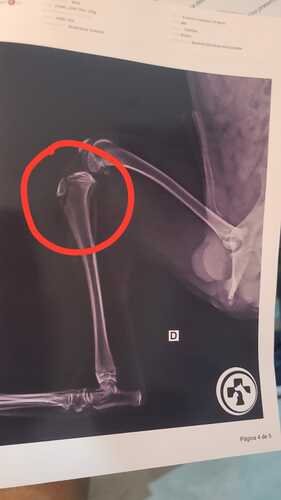

(05/06) Oi, eu sou o Max eu fui atropelado e tenho duas fraturas na minha perninha. Meu AUmigo me resgatou, me levou no médico e está cuidando de mim, mas as depesas são muito caras e ele não consegue pagar sozinho.

A cirurgia e os gastos inclusos (remedios, internação, exames) giram em torno de R$ 7.000,00 reais. Me ajude, por favor, sozinho meu AUmigo não consegue dar conta. Eu preciso MUITO da ajuda de vocês, muito AUbrigado por qualquer ajuda. Lambeijos do seu amigo MaX!